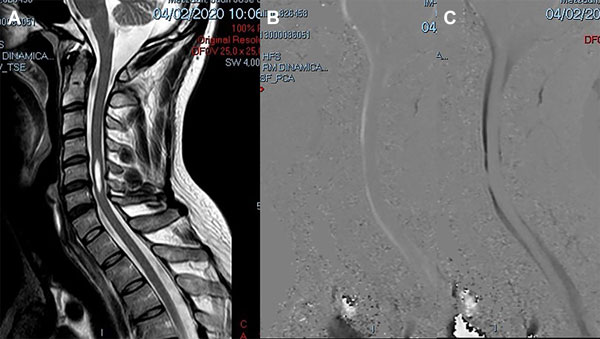

Un varón de 38 años de edad consultó por haber padecido una cérvico braquialgia derecha 30 días antes. En el momento de la consulta sus síntomas habían desaparecido y el examen neurológico fue normal. La RM mostró discopatías cervicales múltiples con una dilatación quística en la médula cervical a nivel C5-C6 que no tomaba el contraste con gadolinio (Figura 6A). Para profundizar el diagnóstico diferencial se realizó una RM en contraste de fase para medir la velocidad del LCR a nivel del canal cervical. La velocidad medida fue de 11 cm/seg (Figura 6B-C). Se hizo el diagnóstico de SM espinal primaria causada por una discopatía cervical a nivel C5-C6. Como el paciente estaba asintomático sólo se indicó control periódico. En su última evaluación, 2 años después, la situación clínica e imagenológica no había cambiado por lo que se mantuvo la misma conducta.

Figura 6: Caso 4. A: RM de columna cervical en plano sagital ponderada en T2 que muestra una cavidad intramedular entre C5 y C6 compatible con siringomielia. B: Estudio de dinámica de LCR que muestra una imagen de magnitud en fase anterógrada con señal hiperintensa el flujo en sístole con disminución del pasaje del LCR en C5-C6. C: Estudio de dinámica de LCR que muestra una imagen de magnitud en fase retrógrada con señal hipointensa el flujo en diástole con la alteración del pasaje de LCR a nivel C5-C6.